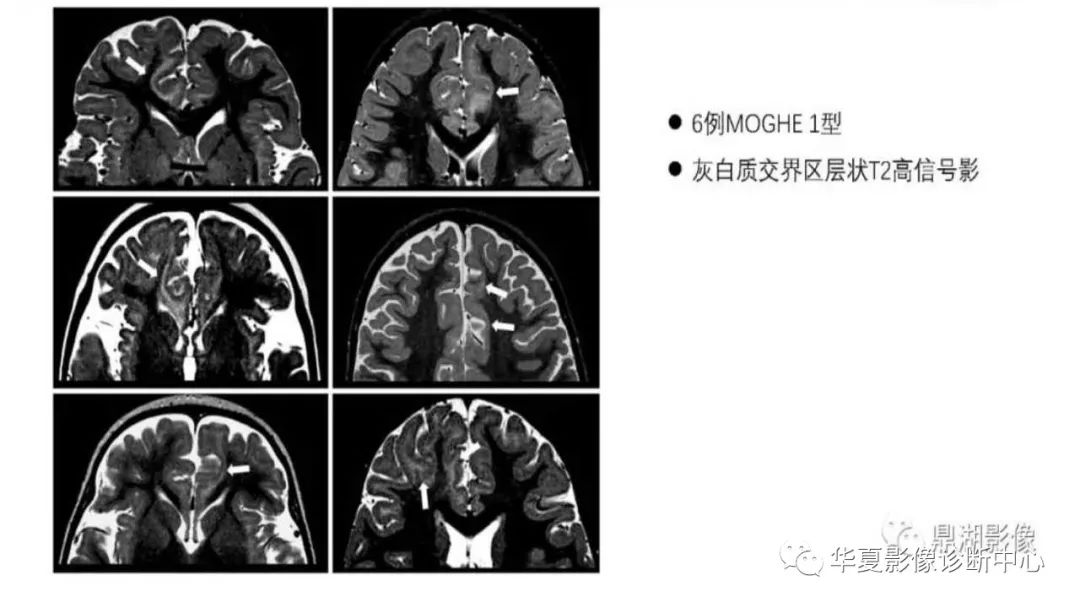

MOGHE的MRI诊断与鉴别诊断-3